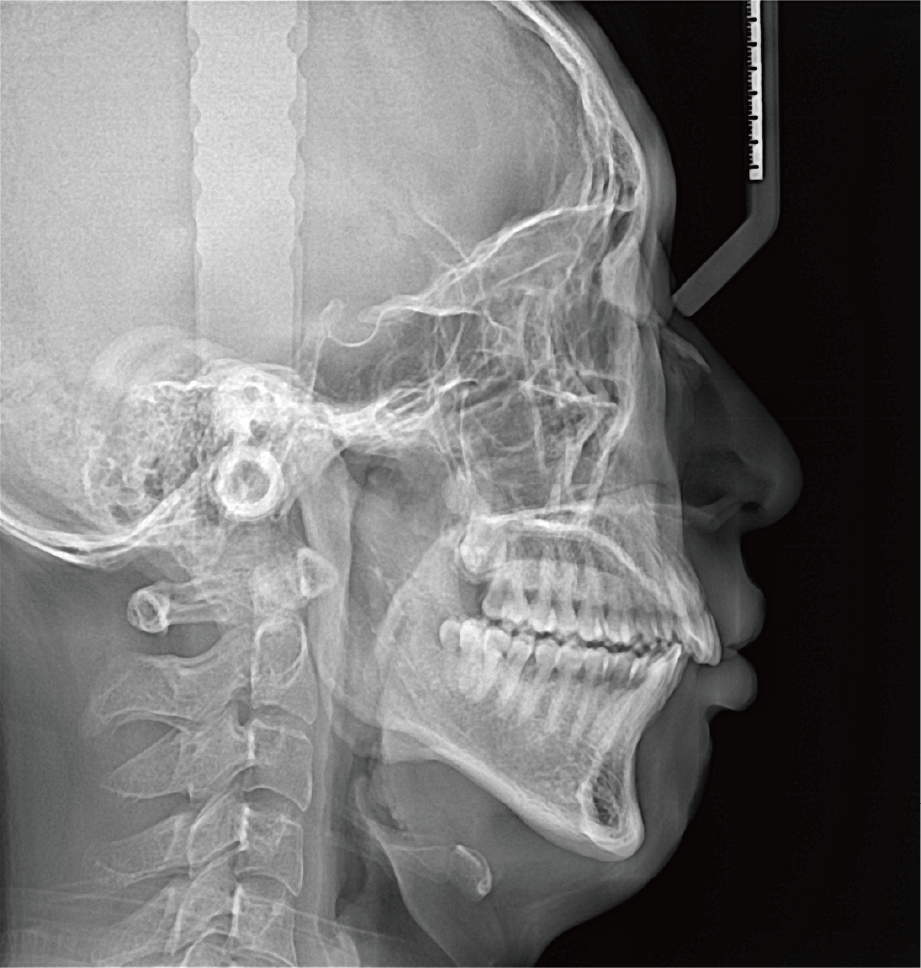

真人正侧位投影,实现CT成像区域无极可调

临床样片